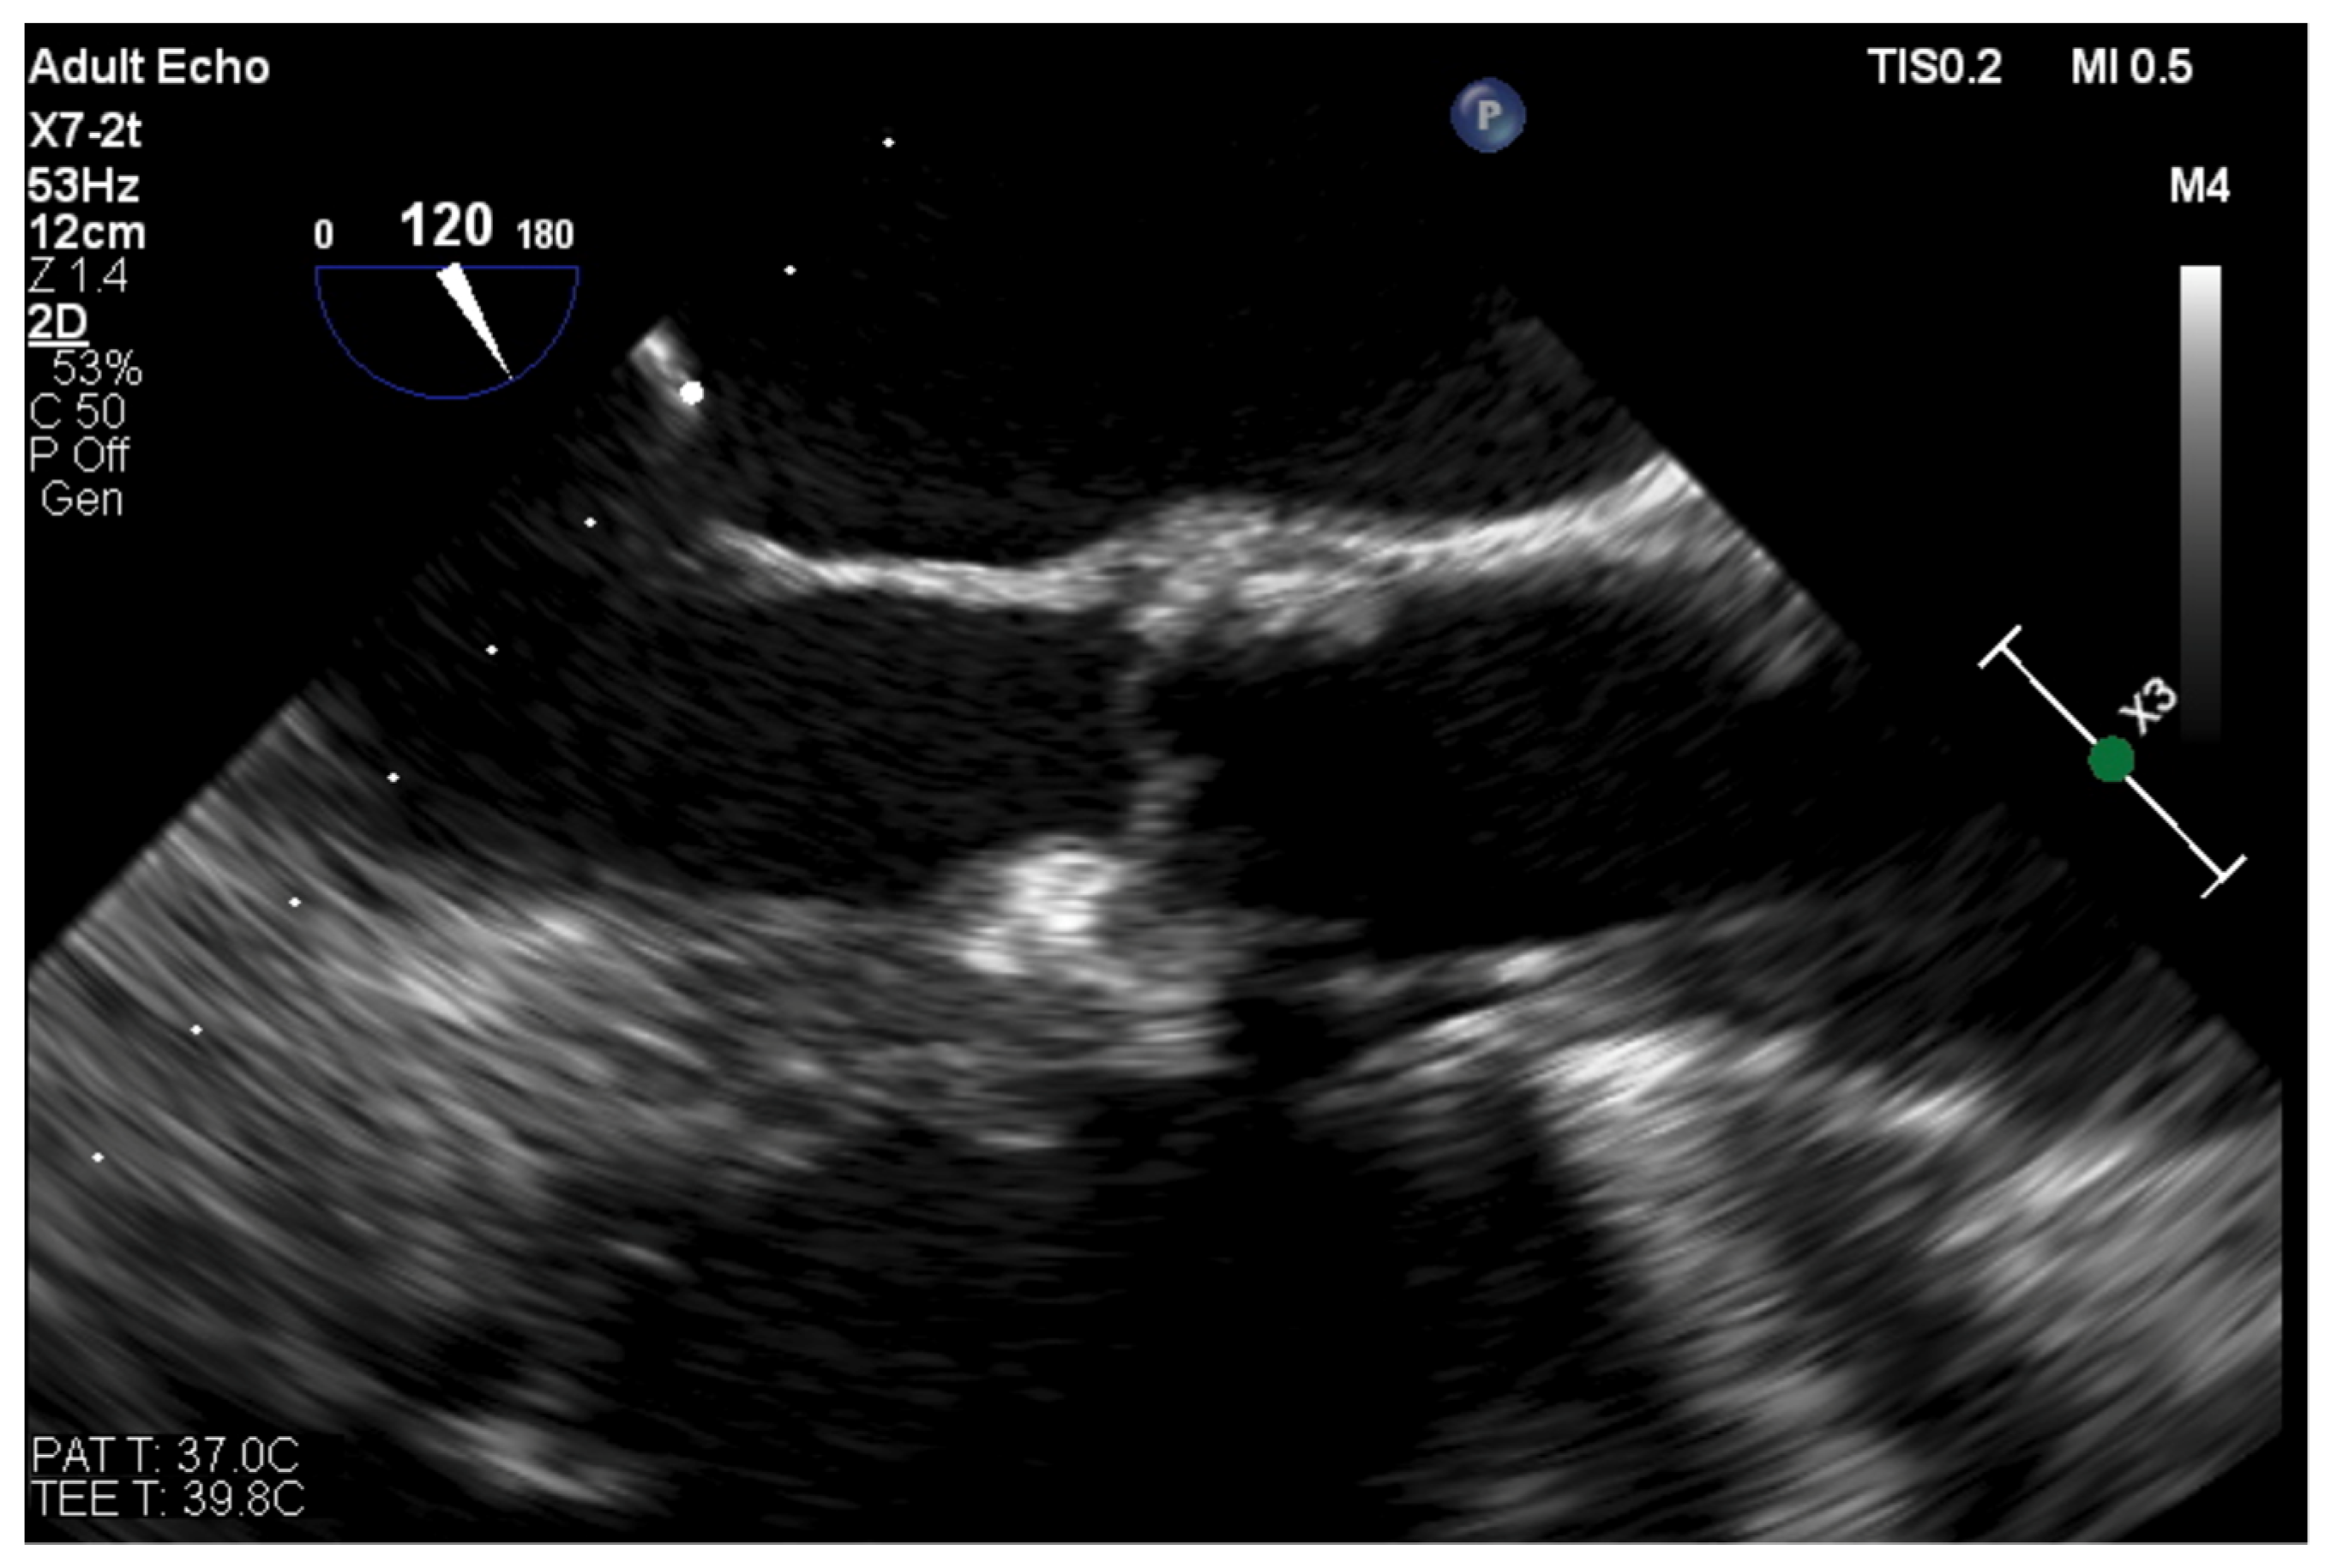

The directions of motion are identified in a standard manner in regard to the superior (SVC) and inferior (IVC) vena cava (superior: towards the SVC; inferior: towards the IVC) and aorta (anterior: toward the aorta; posterior: opposite the aorta). Increasingly, in selected patients, intuitive guidance by 3D volume rendering is possible. See Figure 4.

Figure 4. 3D TOE volume rendering visualization of the interatrial septum tenting (black arrow) produced by the tip of transseptal sheath (IVC: inferior vena cava; Ao: aortic root).